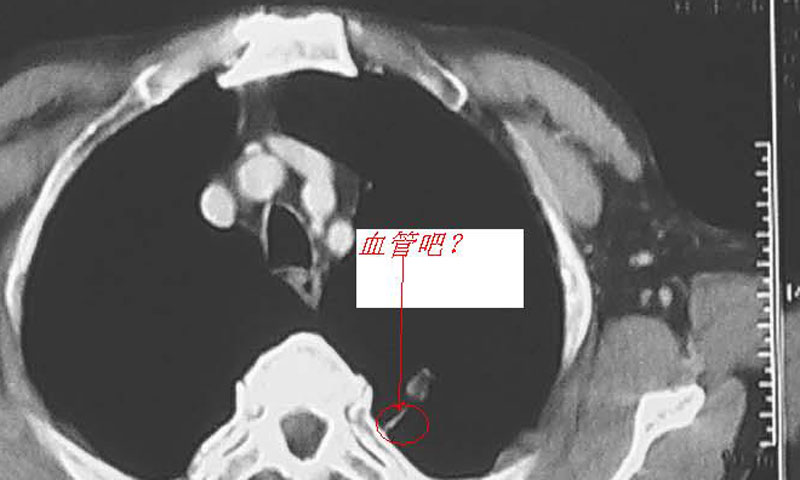

首先不考虑恶性的,因为病灶表现边缘平直形成方块征。虽然位置偏上,但是与脊柱间有血管影,会不会是起源于肋间神经的血管?如果是那就考虑肺隔离征(见下图)

肿块呈方形,边缘尚光滑;似见强化(无ps比较),病灶基底部见蒂状结构,临近血管受推,考虑为肺外病变,源于胸膜可能性大,如局限性胸膜间皮瘤,当然是不能除外炎性假瘤。恶性特征不明确暂不考虑肺癌。